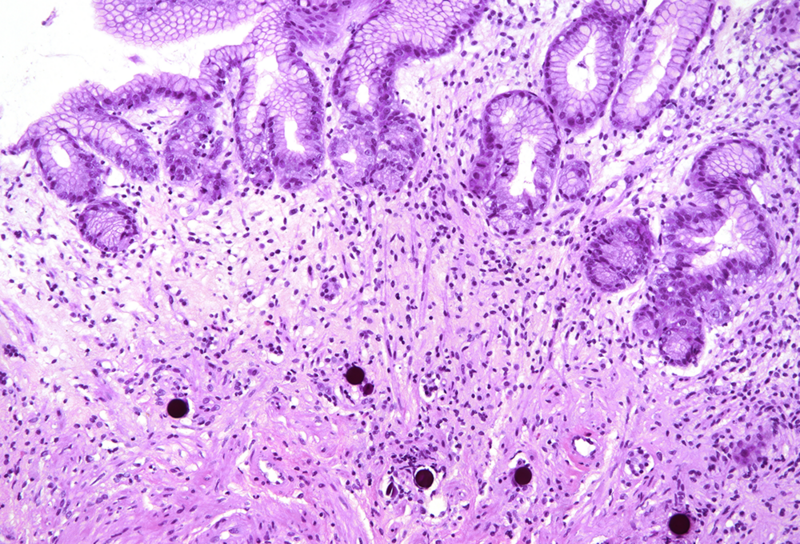

Histologically, in the duodenal bulb and all gastric biopsies was visible a blueish spherical foreign material in the stroma, inside small blood vessels, which corresponded to the given chemoembolization medium – yttrium-90 microspheres. Surface mucosa of all samples showed reactive and inflammatory changes with atrophic areas (Panels A-D).

Selective internal radiation therapy (SIRT) is increasingly used for the treatment in non-resectable primary or secondary liver malignancies by injecting intra-arterially radioactive yttrium-90 microspheres. However, due to rich vascularisation of the liver and surrounding organs, migration of microspheres is possible, leading to complications. The most common complications are involving GI tract – gastritis, gastrointestinal ulcers, cholecystitis and liver disease, and non-GI - radiation pneumonitis. That is why awareness of these complications and multidisciplinary approach are necessary for patient’s overall well-being. The pathophysiological mechanism behind gastric injury is not fully understood, but seems to be due to chronic and persistent ischemic injury to the mucosa of the stomach, leading to ulceration and inflammation in the viable mucosa. Please note that reactive cytological and nuclear changes may be marked, thereby mimicking dysplasia (a dangerous caveat).